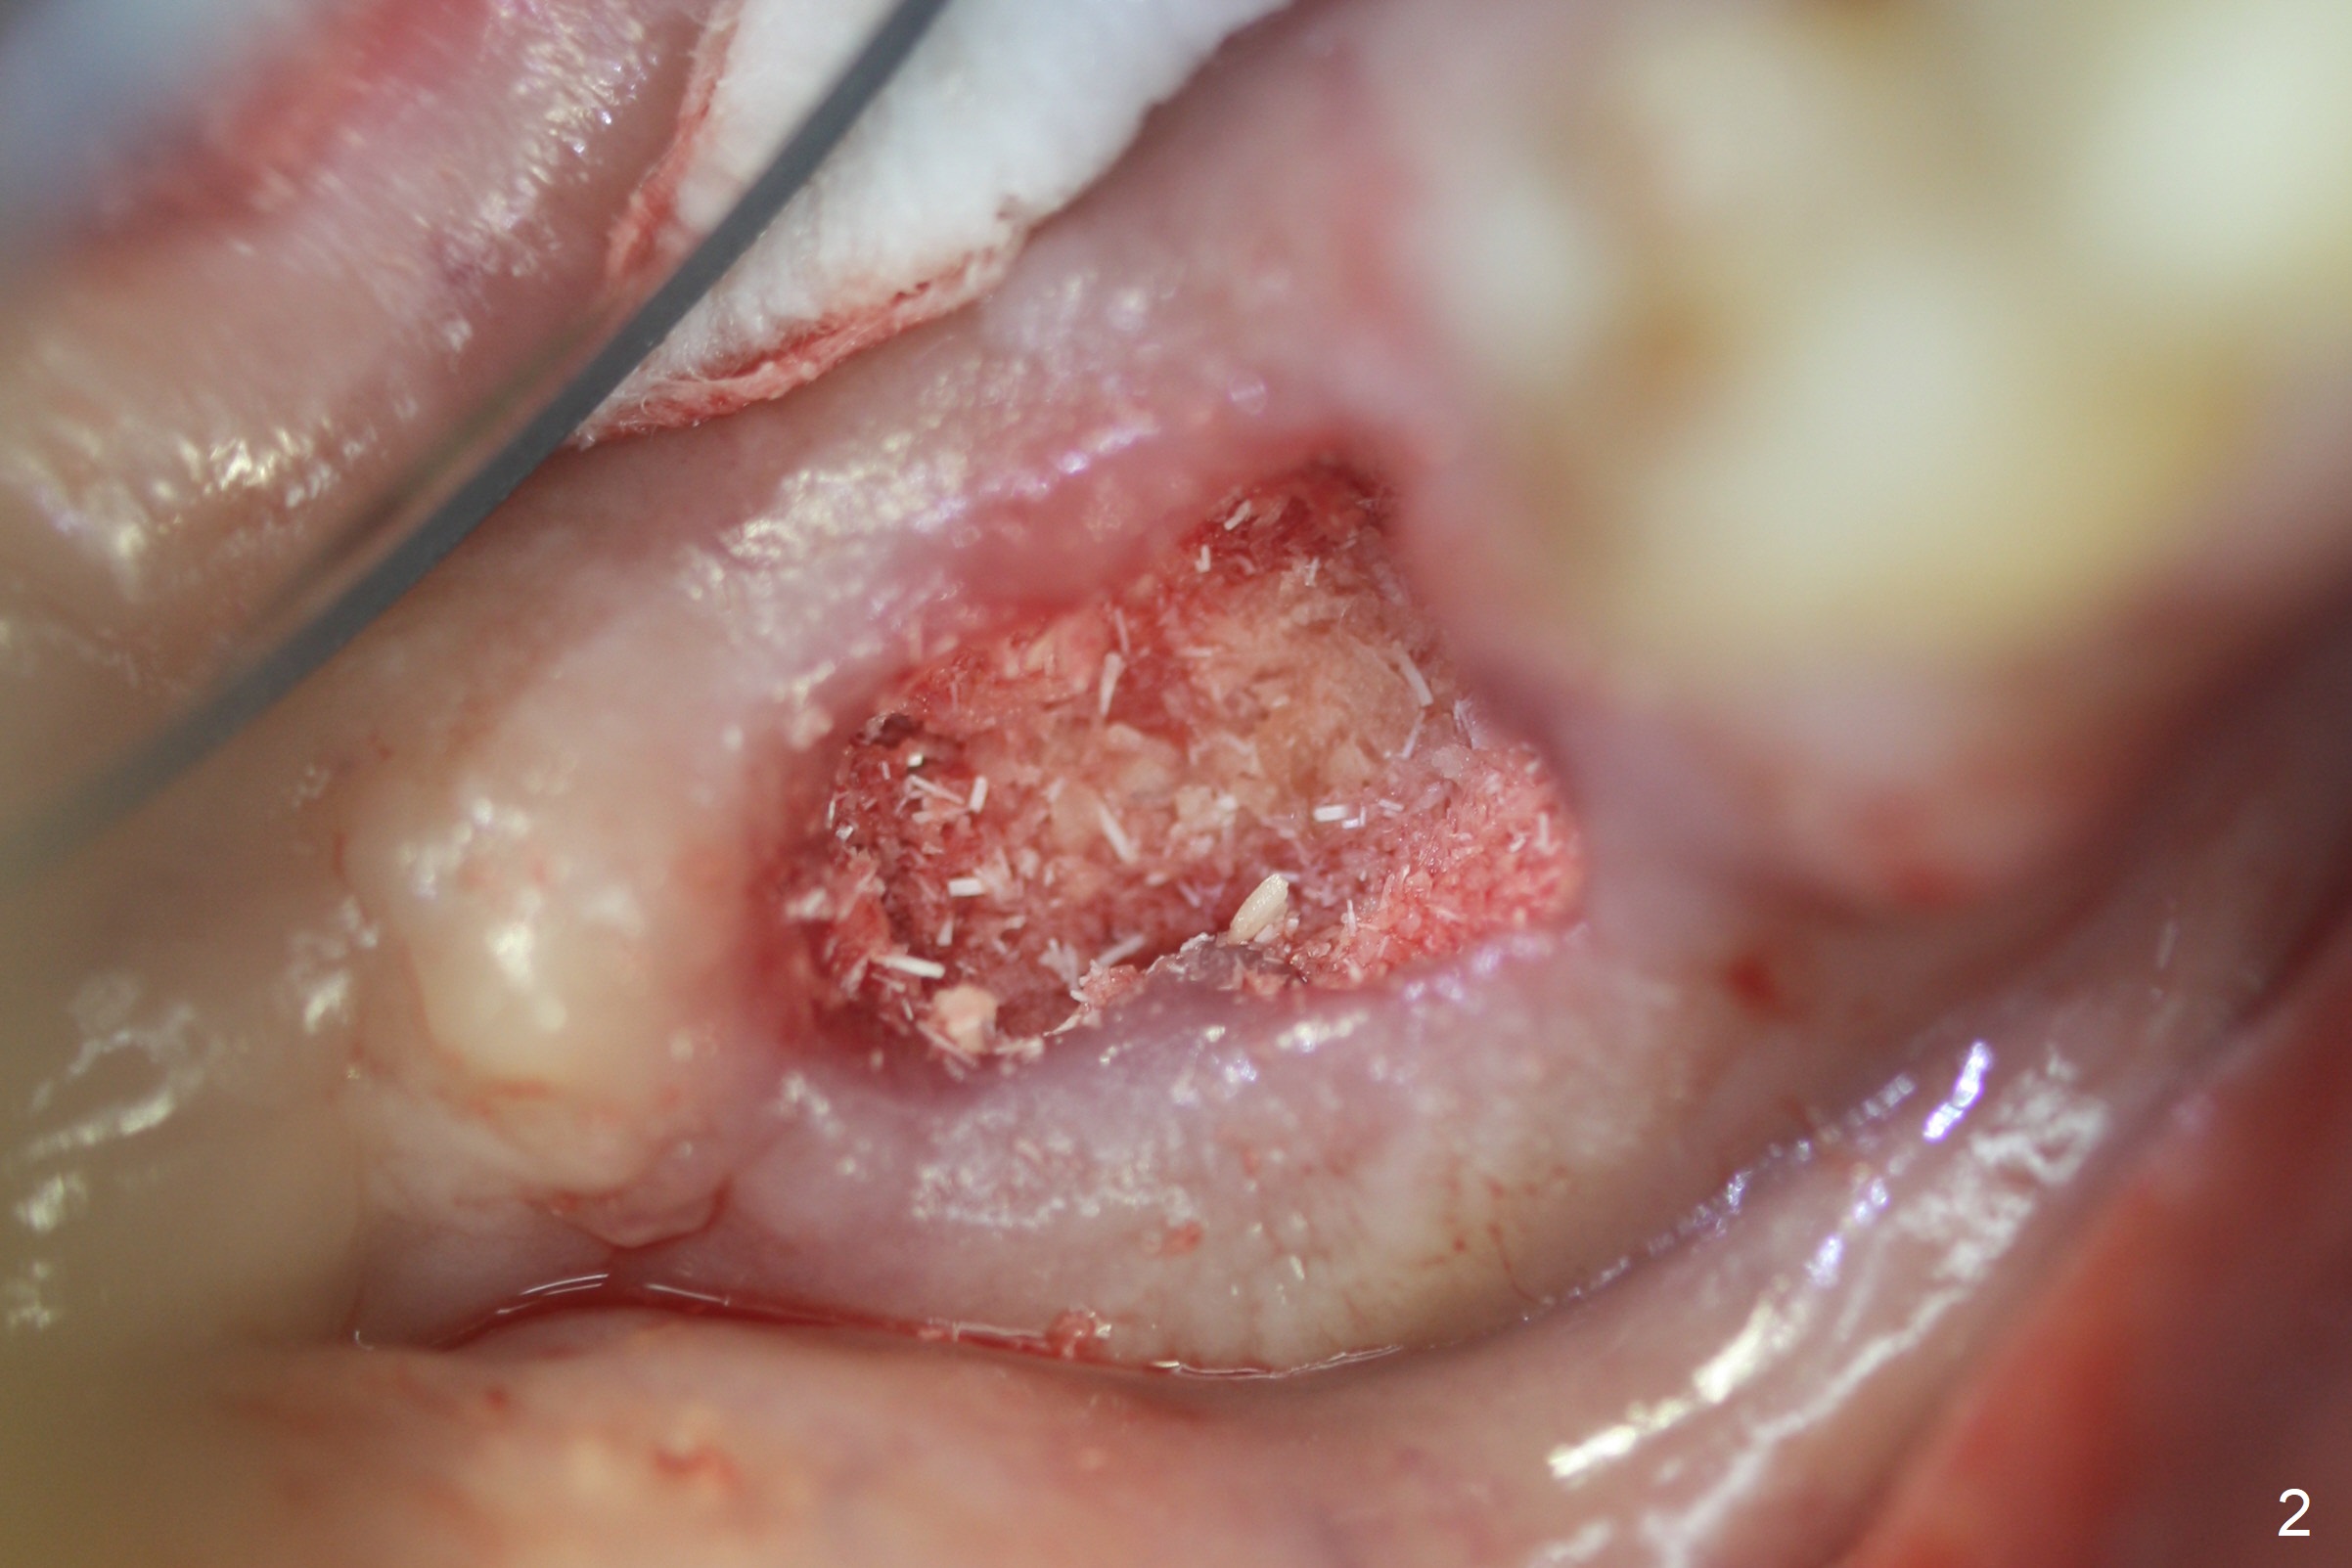

Extraction of the mobile tooth #31 (Fig.1) and debridement of the large socket are not difficult. But making osteotomy buccally does not seem to be easy. It will be difficult to restore. Instead, socket preservation is accomplished by filling the socket with approximately 1.5 cc of Mineralized Cortical/Cancellous allograft until the crest (Fig.2,5). The socket opening is closed by insertion of 4 pieces of PRF membranes (Fig.3) and 4-0 Chromic gut sutures (Fig.4). In the end of surgery, it appears that osteotomy in the center of the socket could be a better approach. Postop re-analysis of CT (Fig.6) and PA (Fig.7) shows that there is 3.9 mm of the native bone to support a 5.5x10 mm implant. Sinus Lift Master Kit should be used with 2 mm initial drill and 2.8 and 3.6 mm round drills with 4 mm stopper.